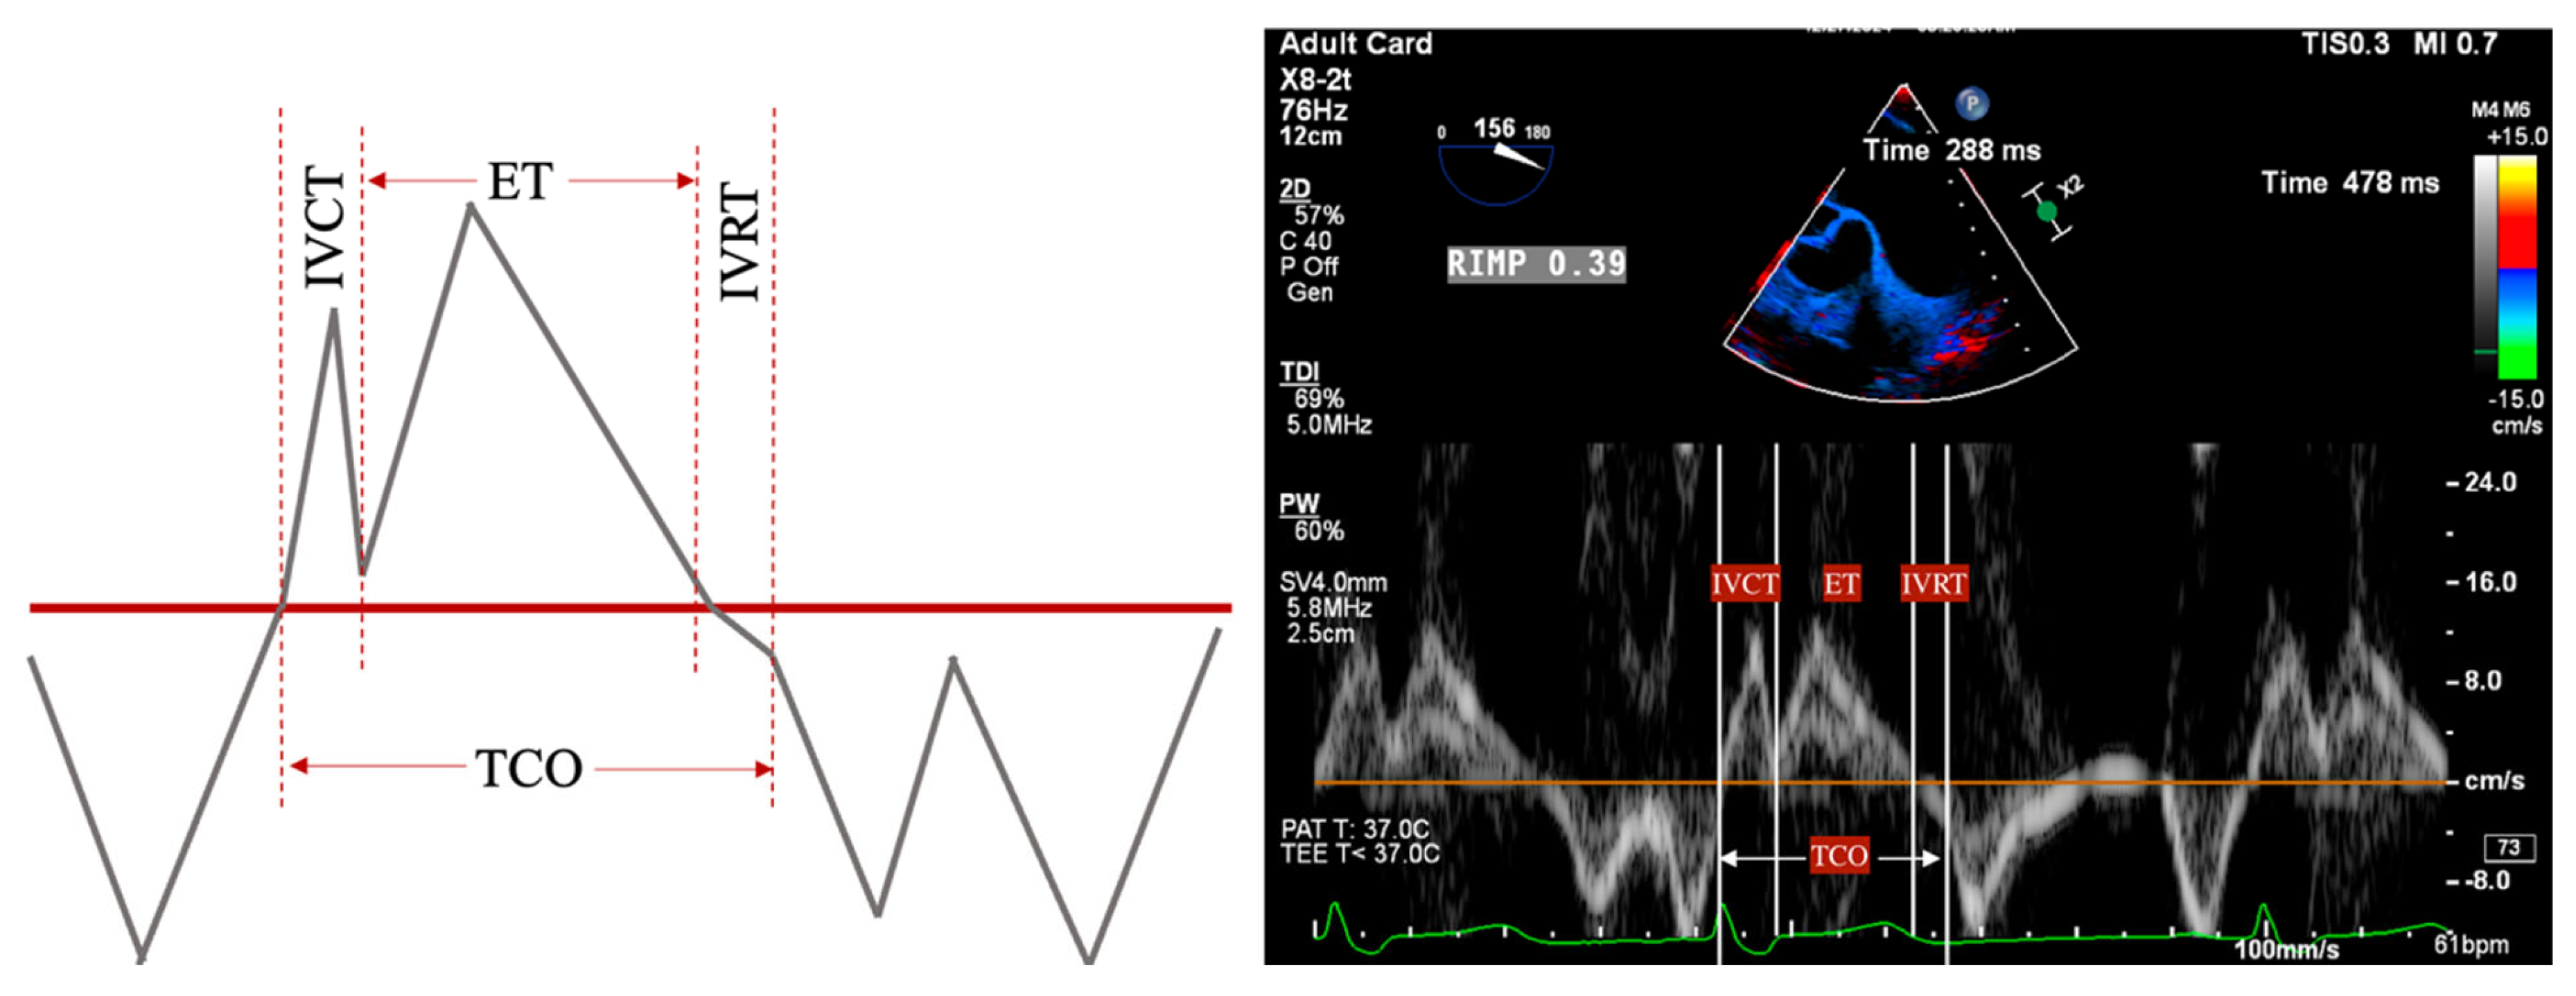

- PR Index: The ratio of PR duration and total diastolic time (regurgitation time/diastole); <0.77 is consistent with severe PR (Figure 2).